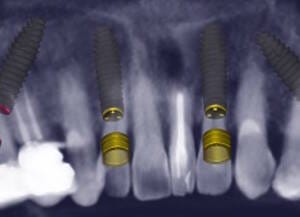

Natalie’s treatment began with a comprehensive clinical assessment, including a review of her medical and dental history, a full examination, and analysis of her functional difficulties such as her tongue habit and altered bite. A 3D cone-beam CT scan was then taken to assess bone quality and volume, identify areas of infection, and map important anatomical structures to ensure safe implant placement.

Alongside this, a digital intraoral scan and detailed photographic records were captured. These provided accurate models of her teeth and bite, as well as valuable information about facial proportions and smile aesthetics. Together, these records ensured that planning would address both the functional and cosmetic aspects of her rehabilitation.

All data were transferred into digital treatment planning software, allowing virtual placement of implants and collaboration with the dental laboratory before surgery. This enabled careful evaluation of long-term outcomes and ensured the design of provisional and final prosthetics could be completed with precision. Following these discussions, the decision was made to proceed with the Fixed-Teeth-in-a-Day approach using the All-on-4 technique.